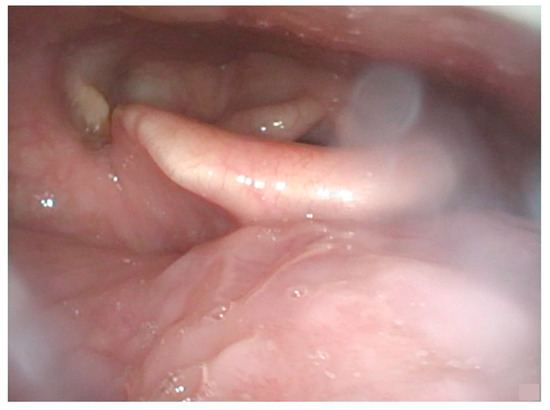

2. Detailed Case Description